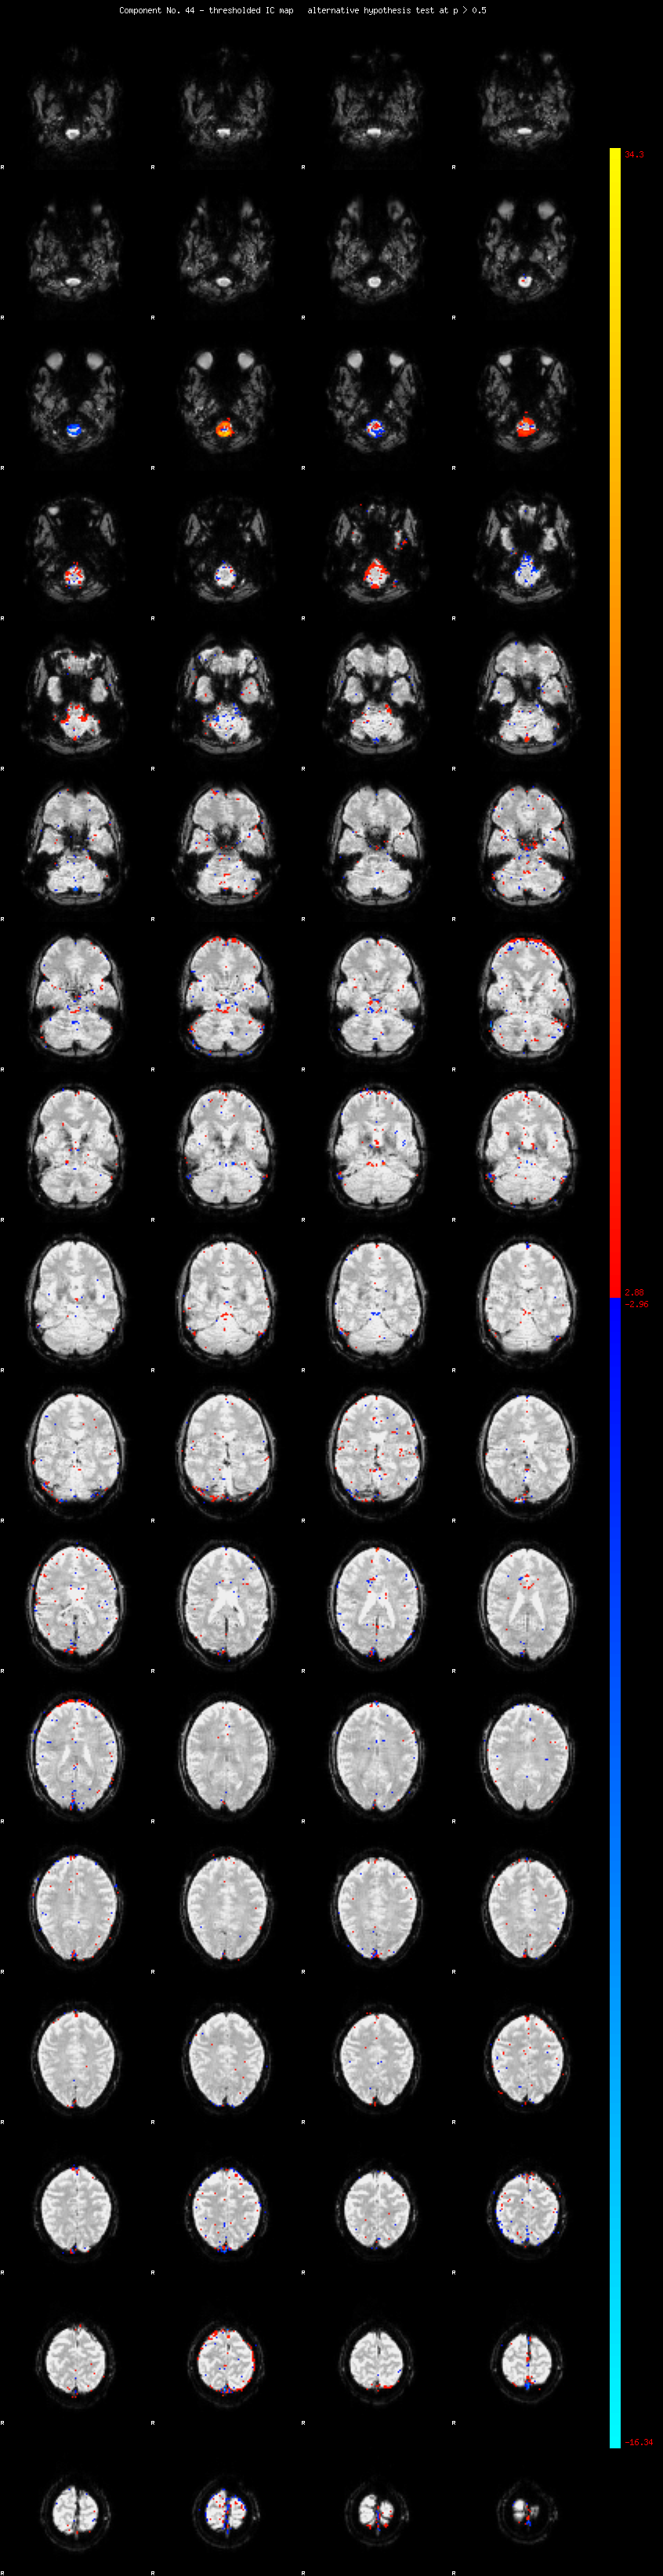

MELODIC Component 44

1.07 % of explained variance;     0.71 % of total variance